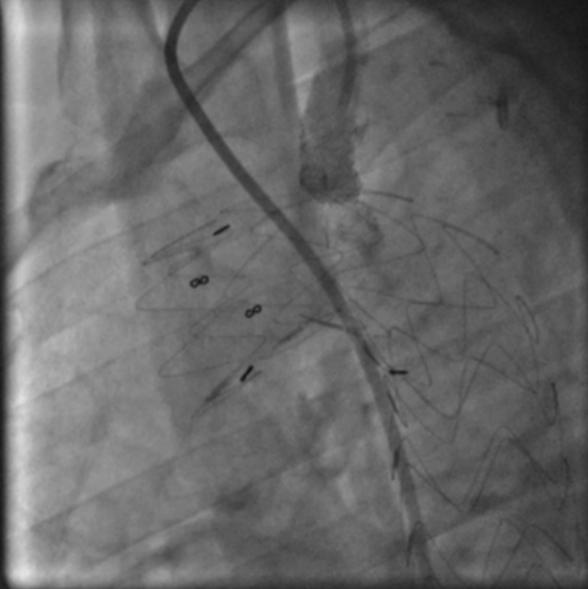

Спасительное ЧКВ

Спасительное ЧКВ тестировалось в исследовании REACT, 2005 [39]. Пациентов после неуспешного тромболизиса1 разделили на 3 группы: 1) группу экстренного (спасительного) ЧКВ (n=144), группу повторного ТЛТ (n=142) и группу консервативной терапии (n=144). Результаты лечения сопоставлялись между группами по числу случаев комбинированной конечной точки. Комбинированная конечная точка объединяла число случаев смерти, реинфаркта, инсульта и тяжелой СН. Число выживших без неблагоприятных исходов к 6 мес. наблюдения составило 84,6% в группе спасительного ЧКВ, 70,1% в группе консервативного лечения и 68,7% в группе повторной ТЛТ (Р=0,004). Авторы заключили, что в группе больных ИМпST после неуспешной ТЛТ спасительное ЧКВ значимо улучшает результаты в сравнении с консервативным лечением или при повторном использовании тромболитика.

Результаты REACT [39] в совокупности с данными анализа, выполненного в исследовании STREAM [17], являются основанием для абсолютных показаний применения спасительного ЧКВ в качестве лечебной стратегии у больных ИМпST с неуспешным восстановлением коронарного кровотока после применения тромболитических средств [1, 2, 7]. Уровень достоверности этих рекомендаций наивысший — А.